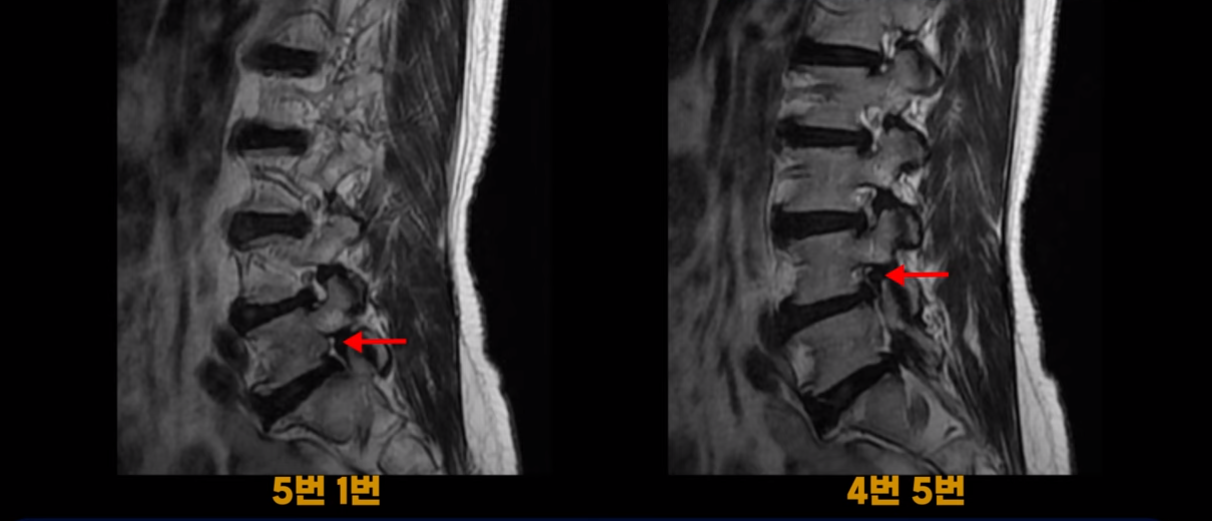

하지만 이 디스크 파열은 오래된 걸로 보이며, 지금 이 환자분의 아픈 양쪽 다리 특히 양쪽 발의 통증, 발 시린 증상과는 관련이 없어 보입니다. 오른쪽 왼쪽의 신경가지가 빠져나가는 추간공을 보면 오른쪽은 5번 1번과 4번 5번이 많이 좁아져 있고

왼쪽은 5번 1번이 많이 좁아져 있습니다.